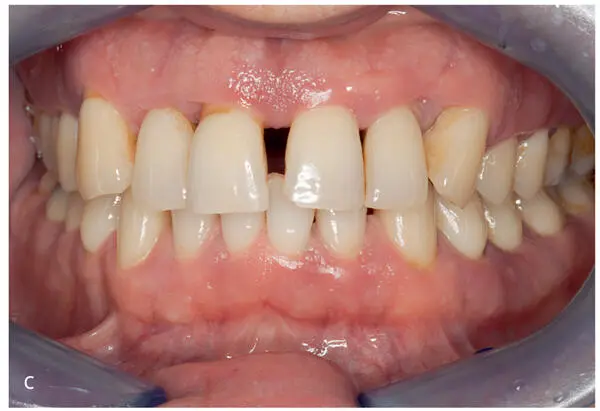

Figs 2-4a to fA 38-year-old (at time of admission) man with an inconspicuous general health and no medication. Diagnosis: periodontitis stage 4, grade C. This case continues in Fig 2-10. Baseline examinations: (a) first and fourth quadrants; (b) second and third quadrants; (c) frontal view; (d) maxillary arch; (e) mandibular arch; (f) baseline measurements of the clinical attachment level, including tooth migration and loosening, furcation involvement, and bleeding on probing (graphic illustration by Parostatus.de).